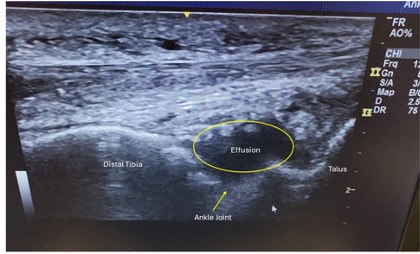

Diagnostic testing. Point-of-care ultrasonography showed tenosynovitis of the peroneal brevis tendon (Figure 1) along with a joint effusion (Figure 2). No clear tophi or double contour sign was noted. A chart review revealed a previous diagnosis of gout. The patient had been on allopurinol 300 mg per day for more than 1 year and was using 0.4 mg colchicine daily for treatment of flare-ups. A recent uric acid level of 3.4 mg/dL was noted. The goal for gout treatment is to have a uric acid below 6, so the patient was seemingly well-controlled. Still, the patient was referred to rheumatology on the clinical suspicion of acute gout attack.

Fig. 2. Long axis view of the ankle joint demonstrating effusion.